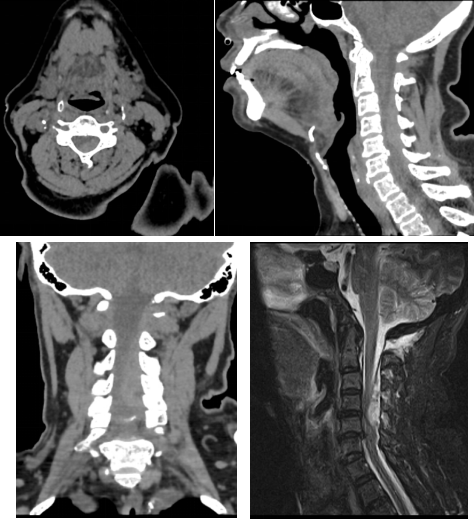

術(shù)前頸椎CT和磁共振:可見明顯血腫占位

通訊員符得紅報(bào)道:近日,63歲譚女士因“頸部疼痛伴左側(cè)肢體癱瘓2小時(shí)”聯(lián)系120后被送至我院脊柱外科,完善頸椎CT、磁共振后考慮“頸椎管內(nèi)出血并頸髓損傷”。體查:頸部活動(dòng)疼痛受限,左側(cè)肢體肌力約Ⅱ級(jí),右側(cè)肢體肌力正常。既往有“高血壓”、“糖尿病”、“心臟病”病史,3年前在外院行“冠脈支架植入”,術(shù)后一直口服“抗凝藥物”抗凝治療。